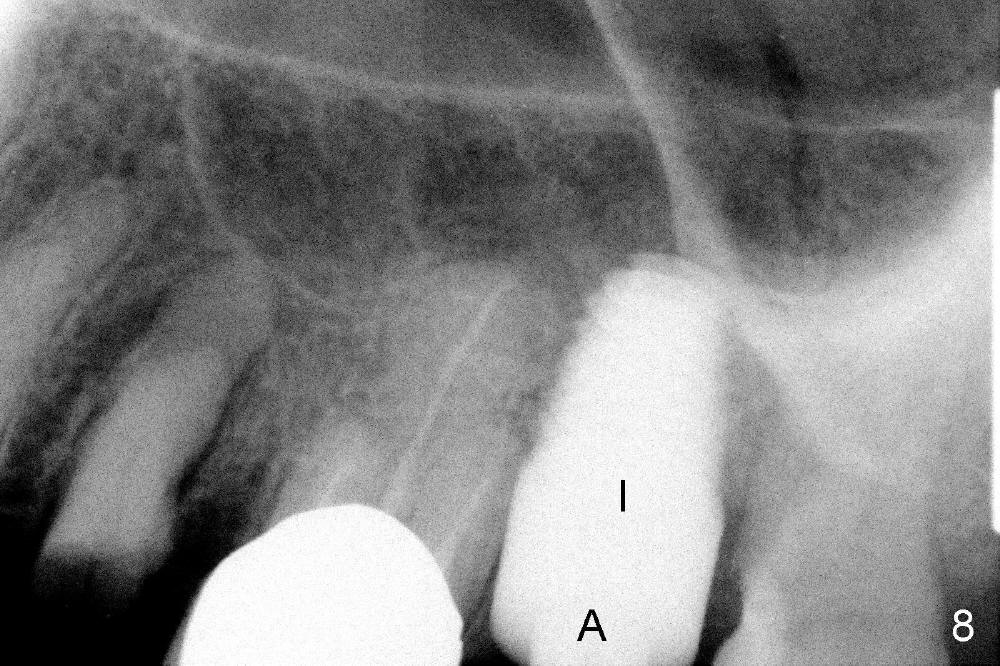

A 66-year-old lady requests restoring a broken tooth (Fig.1). Osteotomy is initiated in a thin septum (Fig.2 (occlusal mirror view) S) by sectioning, drilling and tapping (Fig.3 T). When 7x17 mm tap is removed, the osteotomy is found to form basically in the middle of socket (Fig.4 O). The apical portion of three sockets (Fig.5: MB, P and DB (not labeled) is packed with mixture of autogenous bone and allograft. When a 7x14 mm implant is placed, there are buccal and lingual gaps (Fig.6 *). The latter are bone grafted again (Fig.8 *) and require a coverage. After placement of a 4x3 mm abutment (Fig.7,8 A), an immediate provisional is fabricated (Fig.9 tissue surface view) to cover the remaining sockets (Fig.10 (occlusal mirror view), 11 (buccal view)). The provisional is infra-occlusal, i.e., load-free (Fig.11). The buccal and lingual aspects of the socket are covered by fresh epithelium 8 days postop (Fig.12 <). The implant appears to have osteointegrated 4 months postop (Fig.13). The tooth #16 appears to have shifted mesially. It is difficult to prepare for #15 crown. Luckily the patient agrees to have it extracted because of persistent sensitivity after MO composite. The definitive crown at the site of #15 is cemented 6 months postop (Fig.14).